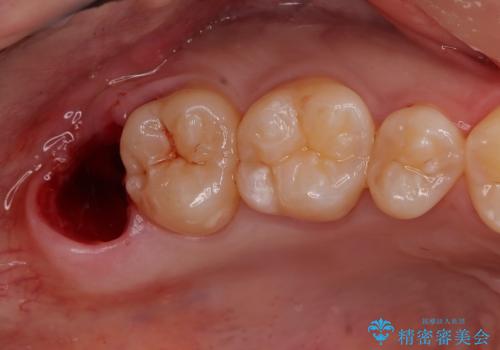

しっかり麻酔が効いているのを確認して抜歯を行いました。

処置は当日行う事が可能です。

- 外科手術のため、術後に出血、痛みや腫れ、違和感を伴います